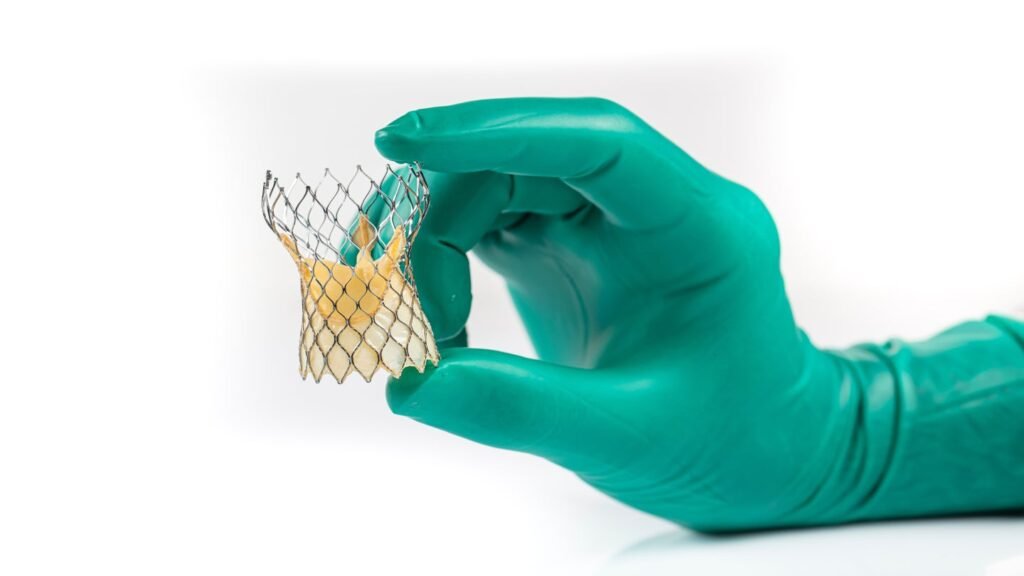

MiRus reports positive results from human trial of Siegel TAVR

The Siegel TAVR system allows increased accessibility for a broader patient demographic, including women. Credit: MiRus. MiRus announced positive results from the first in-human trials of its MiRus Siegel transcatheter aortic heart valve (TAVR). The trial, involving five patients with severe symptomatic aortic stenosis, showed no mortality or stroke at 30 days, and none of […]